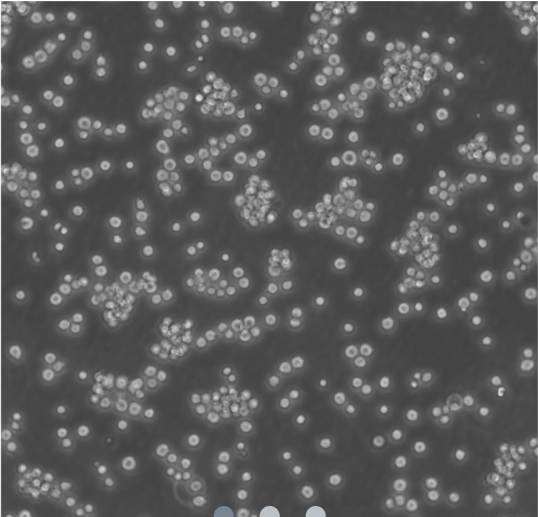

Jurkat cells are a human T-lymphocyte leukemia cell line derived from a 14-year-old with T-cell acute lymphoblastic leukemia (T-ALL). Widely used in research, they’re integral to studies on immune signaling, T-cell activation, HIV infection (via CD4 receptor), autophagy, cytotoxicity assays, and drug efficacy. Jurkat derivatives like E6.1 enhance investigations into signaling pathways and membrane dynamics.